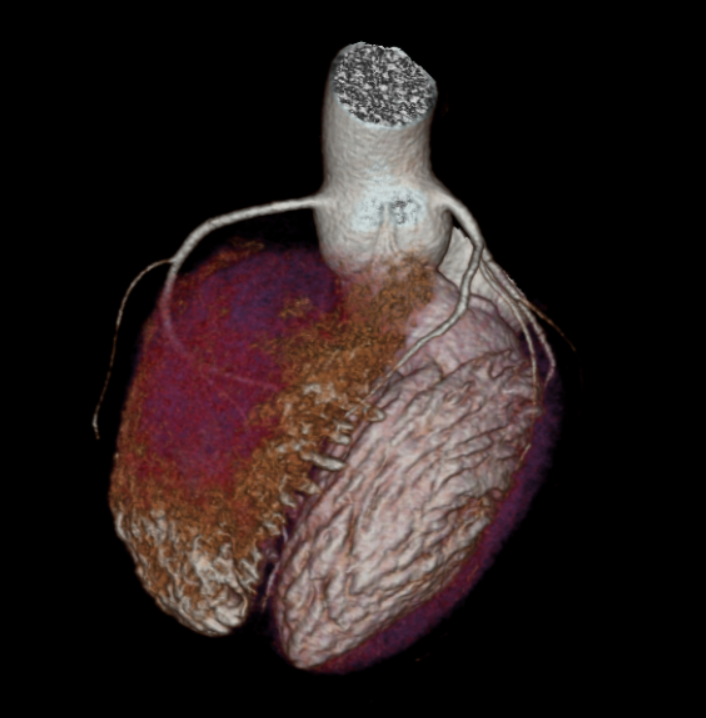

Διεξάγεται σε αξονικό τομογράφο πολλαπλών τομών (>128 detectors) με εξειδικευμένο λογισμικό απεικόνισης και επεξεργασίας των δεδομένων της παλλόμενης καρδιάς. Με την χρήση ακτίνων Χ, υπό ηλεκτροκαρδιογραφικό συντονισμό, διεξάγεται λήψη εγκάρσιων τομών της καρδιάς και με ειδική επεξεργασία δημιουργείται τρισδιάστατη εικόνα του καρδιακού μυ, των καρδιακών βαλβίδων και των στεφανιαίων αγγείων. Στον εξεταζόμενο χορηγείται σκιαγραφική ουσία που δίνει την δυνατότητα ανάδειξης στένωσης ή άλλων ανωμαλιών στις αρτηρίες.

Ακρογωνιαίος λίθος της διαγνωστικής αξίας της αξονικής στεφανιογραφίας είναι η δυνατότητα χαρακτηρισμού των αθηρωματικών πλακών (επασβεστωμένες, μικτής σύστασης, μη-επασβεστωμένες) ανάλογα με το ποσοστό εναπόθεσης ασβεστίου σε αυτές που καθοδηγεί την μετέπειτα κλινική απόφαση και θεραπεία.